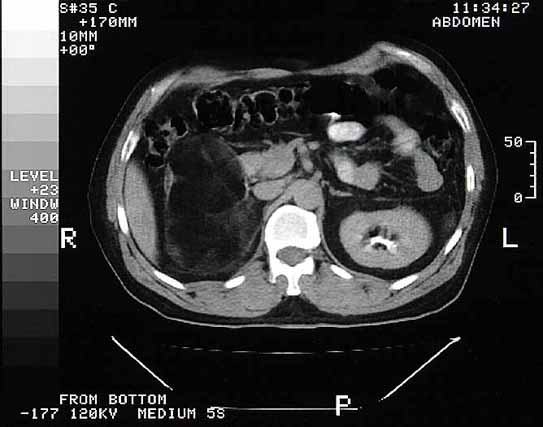

Figura 1. |

Figura 2. |

Figura 3. |

Figura 4. |

Figura 5. |